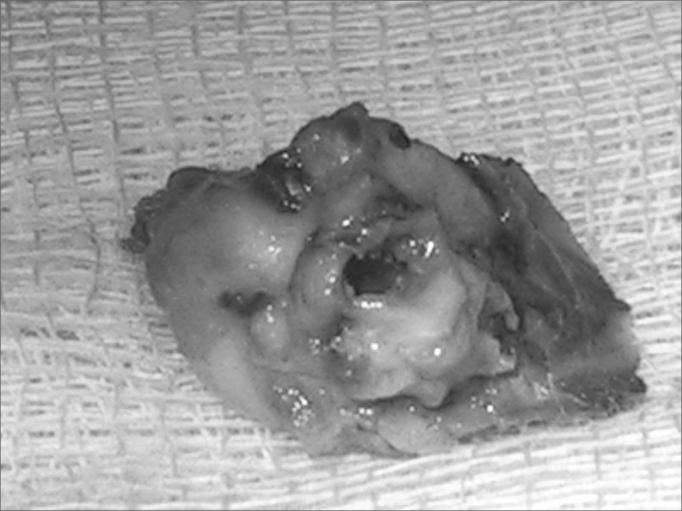

25 guinea pigs were submitted to the application of a 100% propylene glycol solution in their bulla bilaterally and a solution of trans-retinoic acid was applied locally in the external right ear, while in the left ear saline solution was applied (control ear). The guinea pigs were slaughtered and their temporal bones were prepared for macroscopic and histological analysis.

The macroscopic findings had evidenced the presence of cholesteatoma in 25% of the right ears and 85% of the left ears (P=0.0003 ). The histological study had evidenced the presence of cholesteatoma in 30% of right ears and 75% of the left ears (P=0.0104).

The local use of the trans-retinoic acid is effective in inhibiting the induced formation of cholesteatomas in guinea pigs.